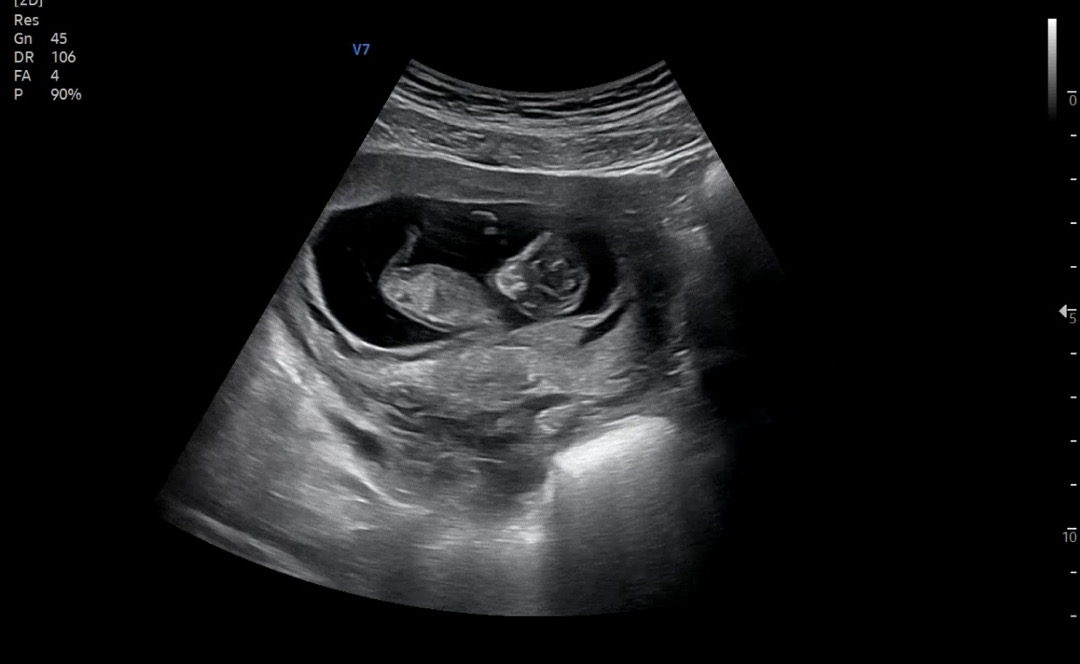

영상으로보면 더잘보일텐데 ㅠㅠ 이사진으론 각도가 안보여용

11주인데 아직 잘 모르겠지만 너무 궁금해서 올려봅니다 뭐 같으신가요??

아직 성기 발달이 안되서 남아 여아 모두 동일하게 보인대요! 좀 더 기다려야할거 같아요 ㅎㅎ 무언가 보셨다면 탯줄일 확률이 큽니다..!

이건 성기로 보일만한게 없어서 알수가 없어요

혹시 각도법으로도 알 수 없을까요?

각도법 찾아보세요~ 각도법도 성기로 추정되는 것의 각도로 보는거예요